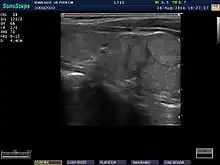

Ultrasound

When patients have normal laboratory values but symptoms of autoimmune thyroiditis, ultrasound plays a role in diagnosis.[6] Images obtained with ultrasound can evaluate the size of the thyroid and further support the diagnosis of autoimmune thyroiditis, reveal the presence of nodules, or provide clues to the diagnosis of other thyroid conditions.[6]